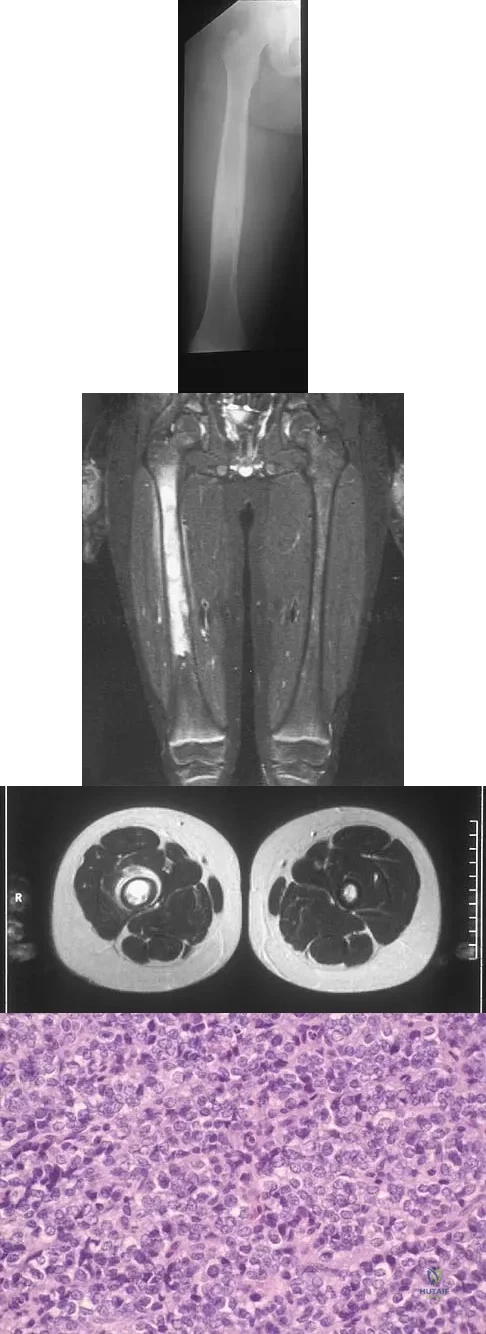

Question 51

A radiograph, MRI scans, and a biopsy specimen of a 9-year-old boy with thigh pain are shown in Figures 37a through 37d. Management should consist of

Explanation